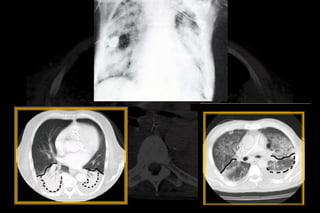

- “Acute lung injury” no longer exists.

- Onset of ARDS must be acute, as defined as within 7 days

- Bilateral opacities consistent with pulmonary edema must be

present but may be detected on CT or chest X-ray.

- There is no need to exclude heart failure in the new ARDS

definition

JAMA. 2012;307(23):2526-2533.